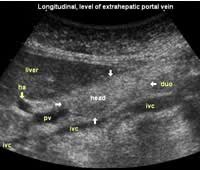

Longitudinal planes from right to left:

![]() Image21 |

![]() Image22 |